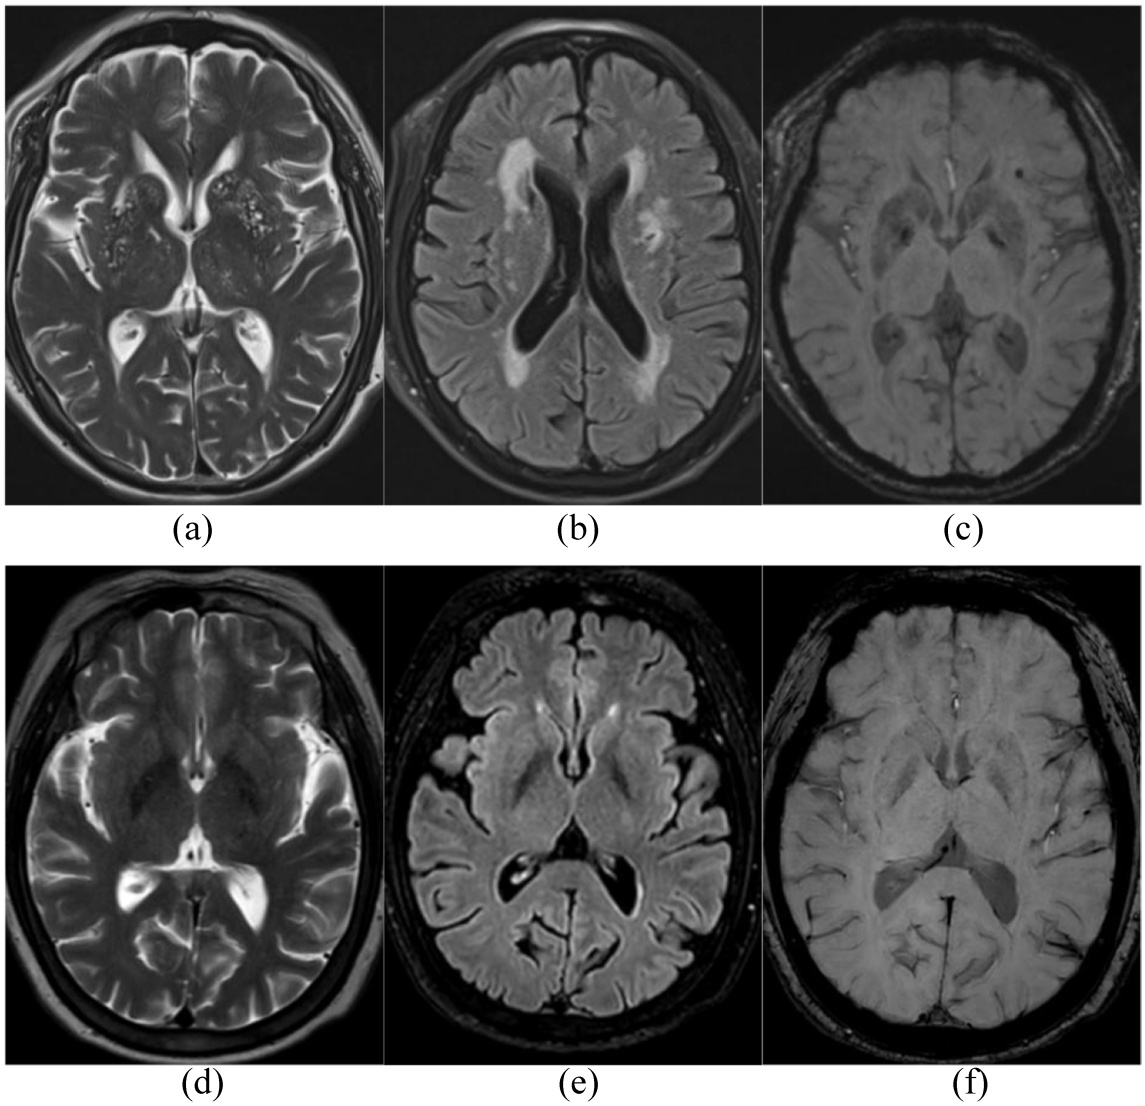

脑小血管病(CSVD)总负荷评分由两名放射科医师独立评估,涵盖腔隙性梗死(LIs)、血管周围间隙扩大(EPVS)、脑白质高信号(WMHs)及脑微出血(CMBs)四项影像学特征,评分标准为:LIs指直径3~20 mm、T2WI及FLAIR呈脑脊液样信号且FLAIR边缘高信号的圆形/卵圆形病灶,≥1个计1分;EPVS指直径 < 3 mm、信号同LIs、好发于半卵圆中心等区域的圆形/卵圆形/线形病灶,>10个计1分;WMHs依据Fazekas量表评估,脑室旁3分和/或深部2~3分计1分;CMBs指直径 < 5 mm、SWI呈低信号的圆形/线形均匀病灶,≥1处计1分[8]。根据总评分将受试者分为无CSVD组(0分,48例)和CSVD组(1~4分,125例),后者进一步分为轻度组(1~2分,95例)和重度组(3~4分,30例),其中评分 > 0分提示存在CSVD,>2分提示严重CSVD (图2)。

Figure 2. Example images of cerebral small vessel disease

2. 脑小血管病示例图

(a)~(c):病例1男,74岁,高血压、糖尿病,吸烟20余年,不饮酒。A. T2WI,双侧基底节区EPVS > 10,记1分,双侧侧脑室旁Lis = 2,记1分;B. FLAIR,WMHs 2~3级,记1分;C. SWI,左侧侧脑室旁CMBs = 1,记1分;CSVD得分4分,CSVD重度组。图(d)~(f):病例2女,65岁,头晕半天,高血压,未见LIs、EPVS、EPVS,FLAIR序列上WMHs 1级,CSVD得分为0分,无CSVD组。